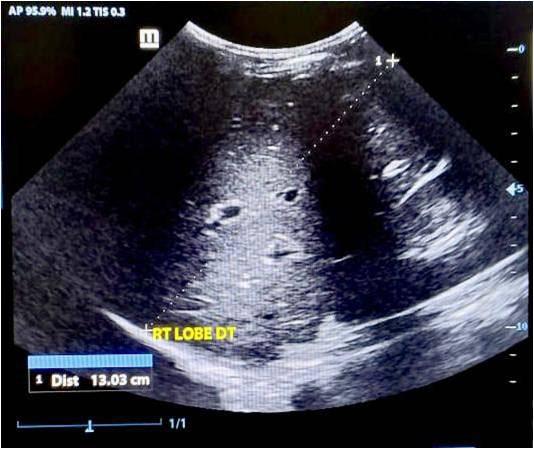

Materials and Methods : This prospective hospital-based study was conducted in the Department of General Surgery, Assam Medical College and Hospital, from January to August 2022. Twenty-five patients diagnosed clinically and radiologically with pancreatic pseudocyst were enrolled. Data on demographics, clinical presentation, etiology, imaging findings, management, and outcomes were collected and analyzed using SPSS v20. Patients were followed up for four months.

Results : Most patients were males (88%) with a mean age of 44.8 years. Alcohol was the predominant etiological factor (72%), and pain abdomen was the universal symptom (100%). Imaging with ultrasonography and CECT abdomen aided diagnosis. Internal drainage was the most common management (40%), followed by external drainage (32%) and conservative treatment (28%). Infection (24%) was the main complication. Recurrence was highest after conservative management.